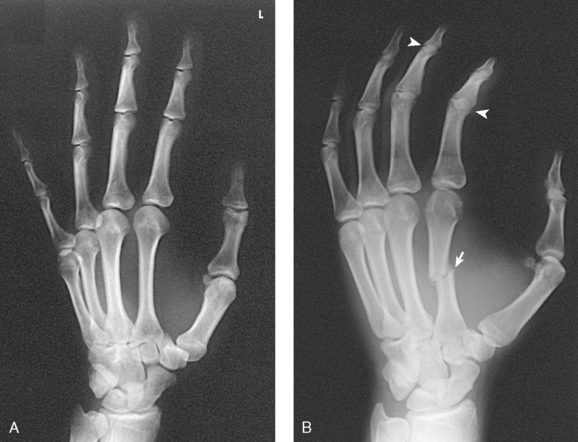

Structures shown: PA projections of the carpals, metacarpals, phalanges (except the thumb), interarticulations of the hand, and distal radius and ulna are shown in Fig. 4-54. This image also shows a PA oblique projection of the first digit.

Structures shown: The resulting image shows a PA oblique projection of the bones and soft tissues of the hand (Fig. 4-58). This supplemental position is used for investigating fractures and pathologic conditions.

Structures shown: The resulting image shows an AP 45degree oblique projection of both hands (Fig. 4-68). The early radiologic change significant in making the diagnosis of rheumatoid arthritis is a symmetric, very slight, indistinct outline of the bone corresponding to the insertion of the joint capsule dorsoradial on the proximal end of the first phalanx of the four fingers. In addition, associated demineralization of the bone structure is always present in the area directly below the contour defect.